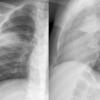

different case

Round pneumonia

Date: 11/28/2009

Views: 6358

Case 2 Lingular pneum PA

Date: 04/17/2005

Views: 6414

Case 2  Lingular pneum Lat

Views: 7427